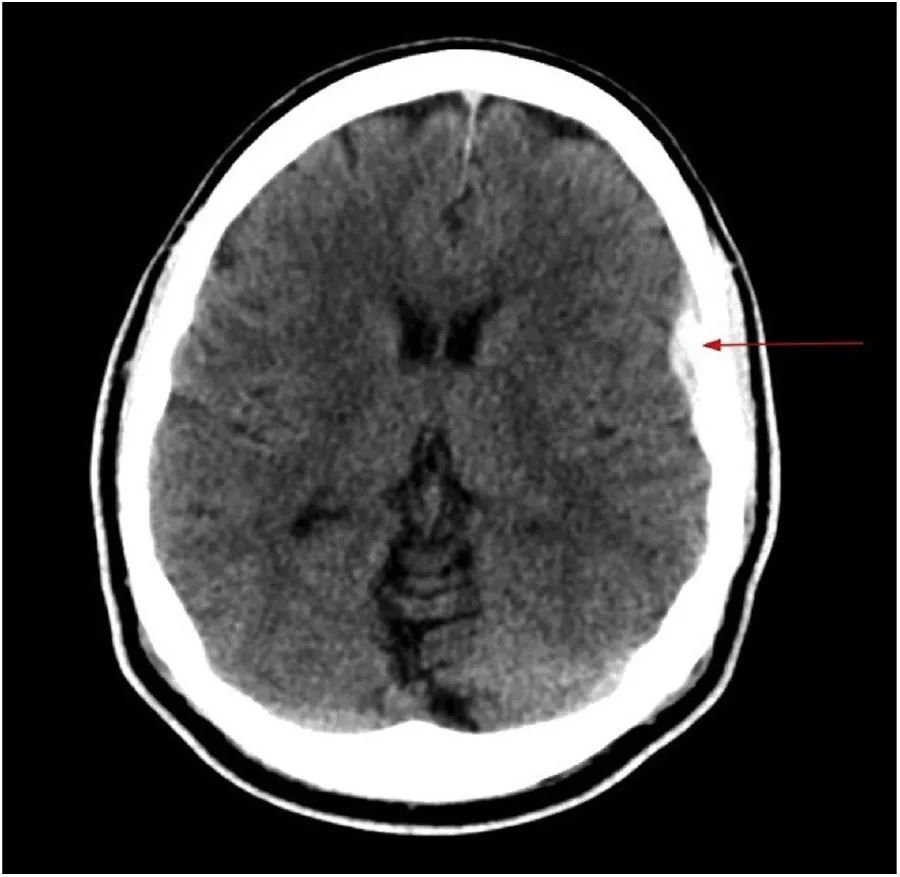

图3 急诊行头部CT显示左额叶皮质上方有少量急性硬膜外出血,没有颅内压升高的表现。

头CT在来诊后6h复查,显示病情稳定。入院第二天进行头颈部CT血管造影,排除血管瘤或动静脉畸形。神经外科医生会诊,建议在神经外科进行密切观察。由于硬膜下血肿很小,不扩大,与颅内压升高或局灶性神经功能缺损无关,因此内科治疗,密切观察。患者住院期间否认发热、呕吐或畏光。

出院后2周复查头部CT显示血肿大小稳定,无扩张或颅内压升高迹象。血压控制良好,随访中。